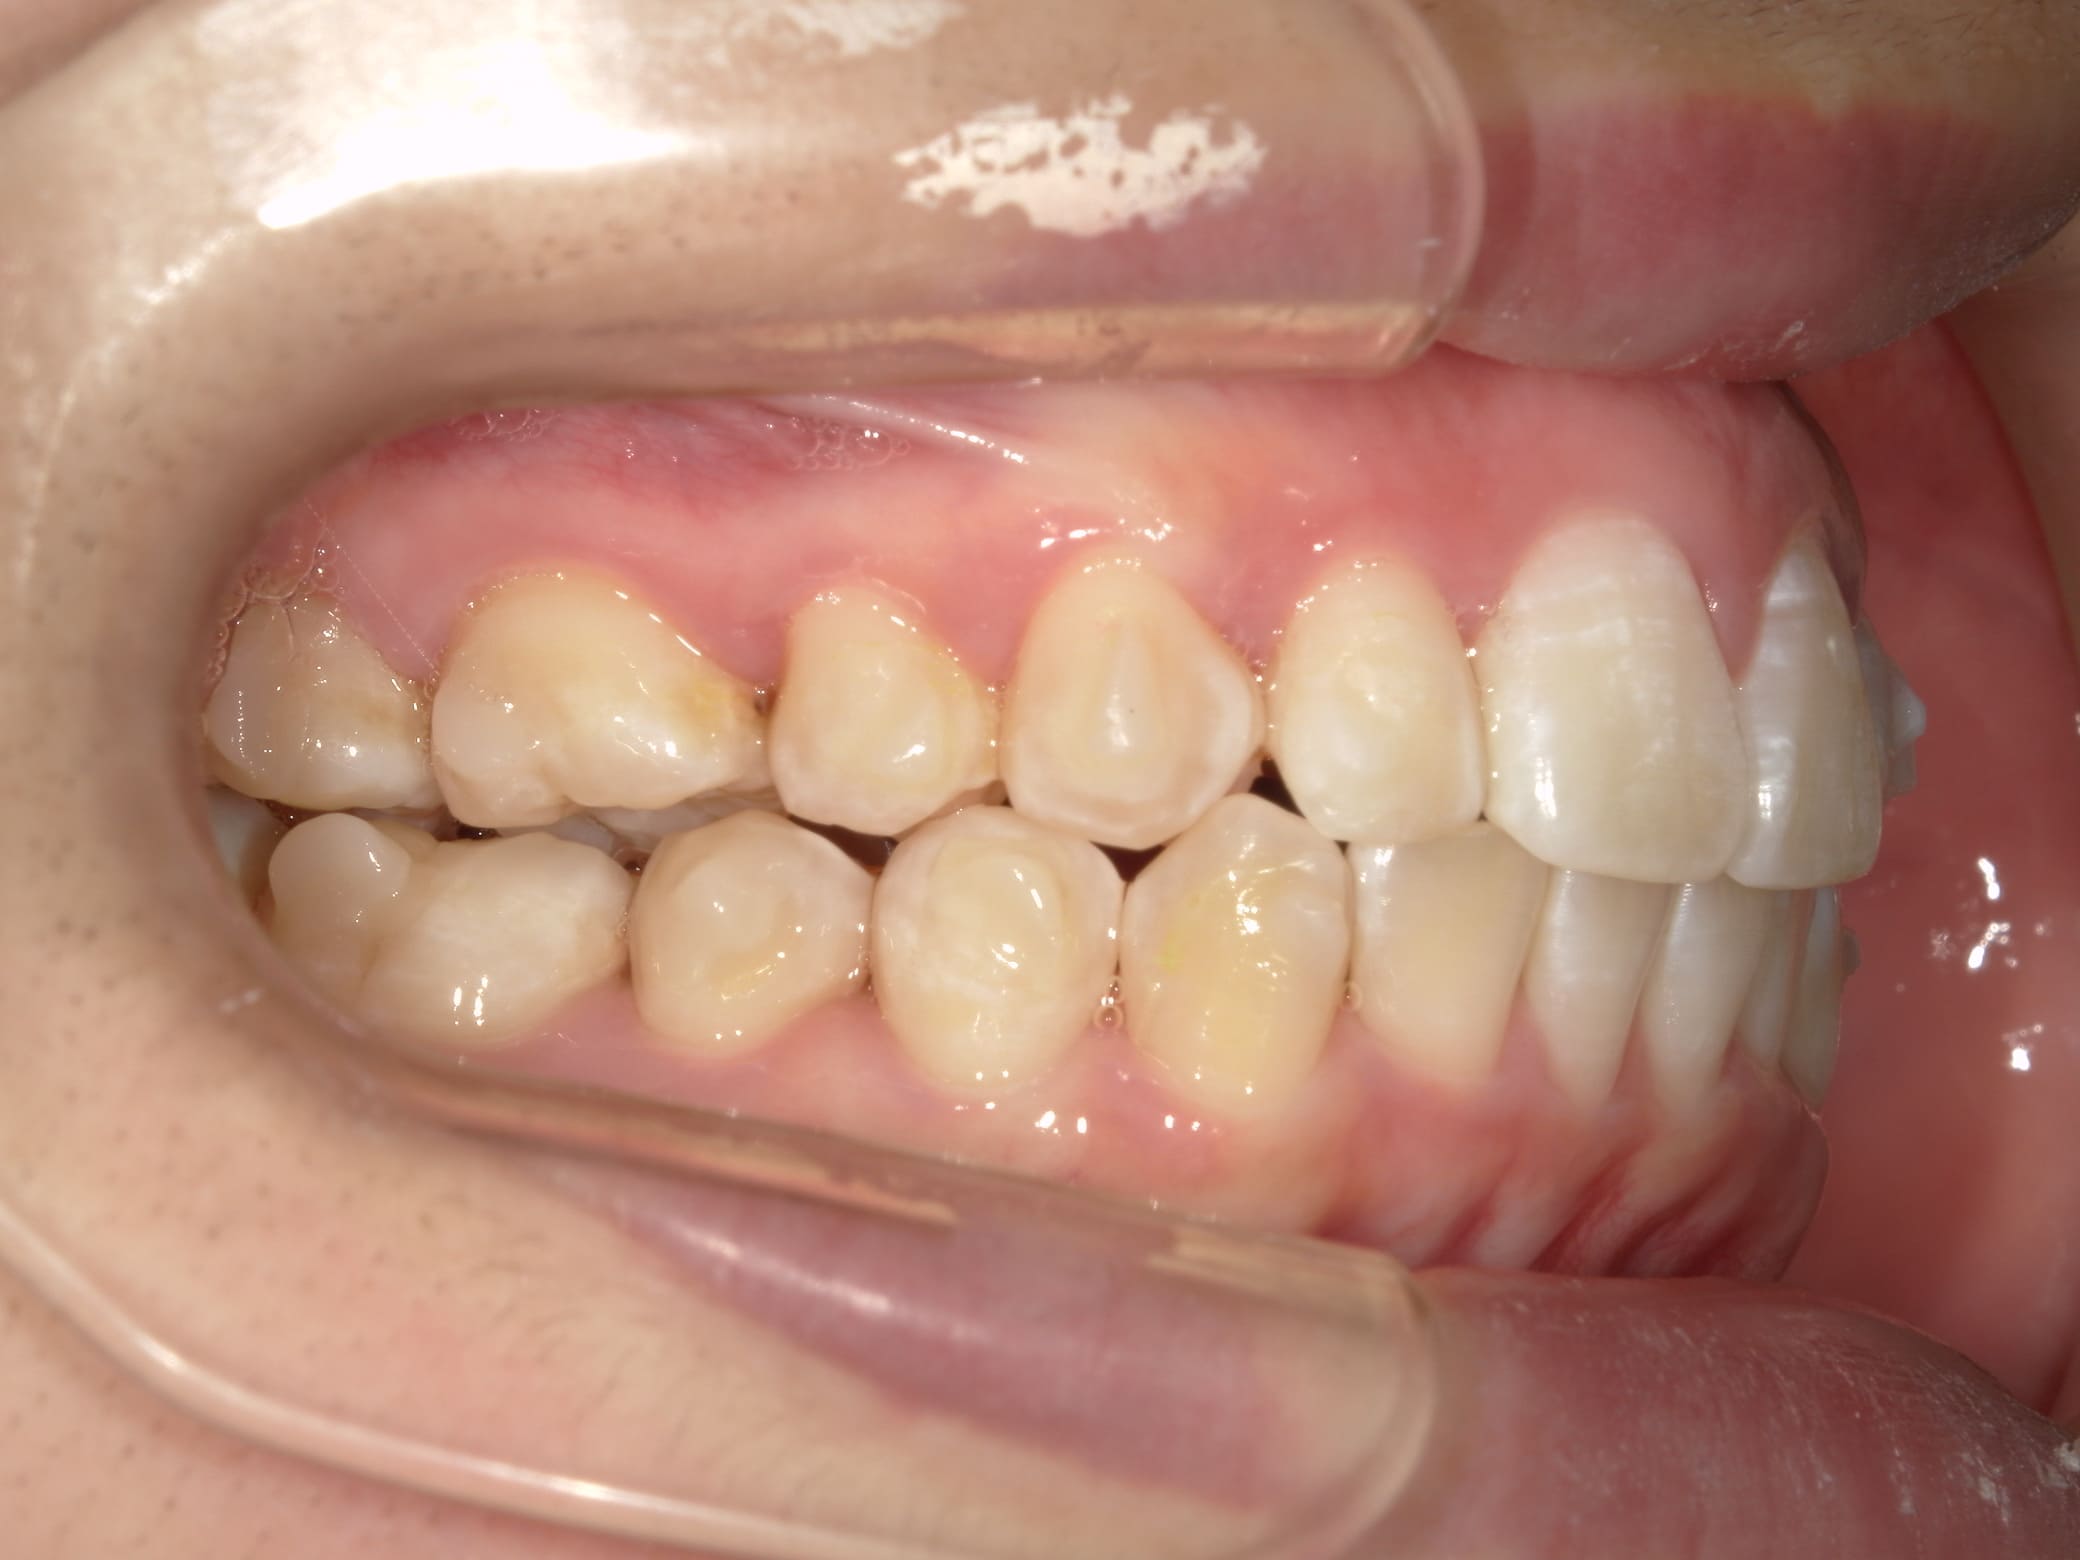

| 年齢・性別 | – |

|---|---|

| 主訴 | 叢生が気になる |

| 治療期間・回数 | 2年 |

| 費用 | 935,000円 |